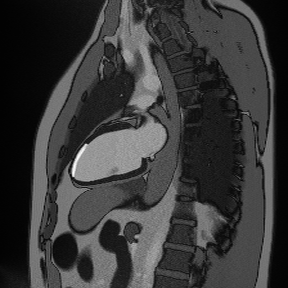

✅ Correct Planning for SAX Late Enhancement:

Correct Planning for SAX Late Enhancement

✅ SAX LGE – Correct Image Example:

Things to Look for in SAX LGE:

• Systematically assess all 17 AHA segments

• Document scar location, size, and transmural extent

• Compare with perfusion defects to identify hibernating myocardium

• Look for papillary muscle involvement